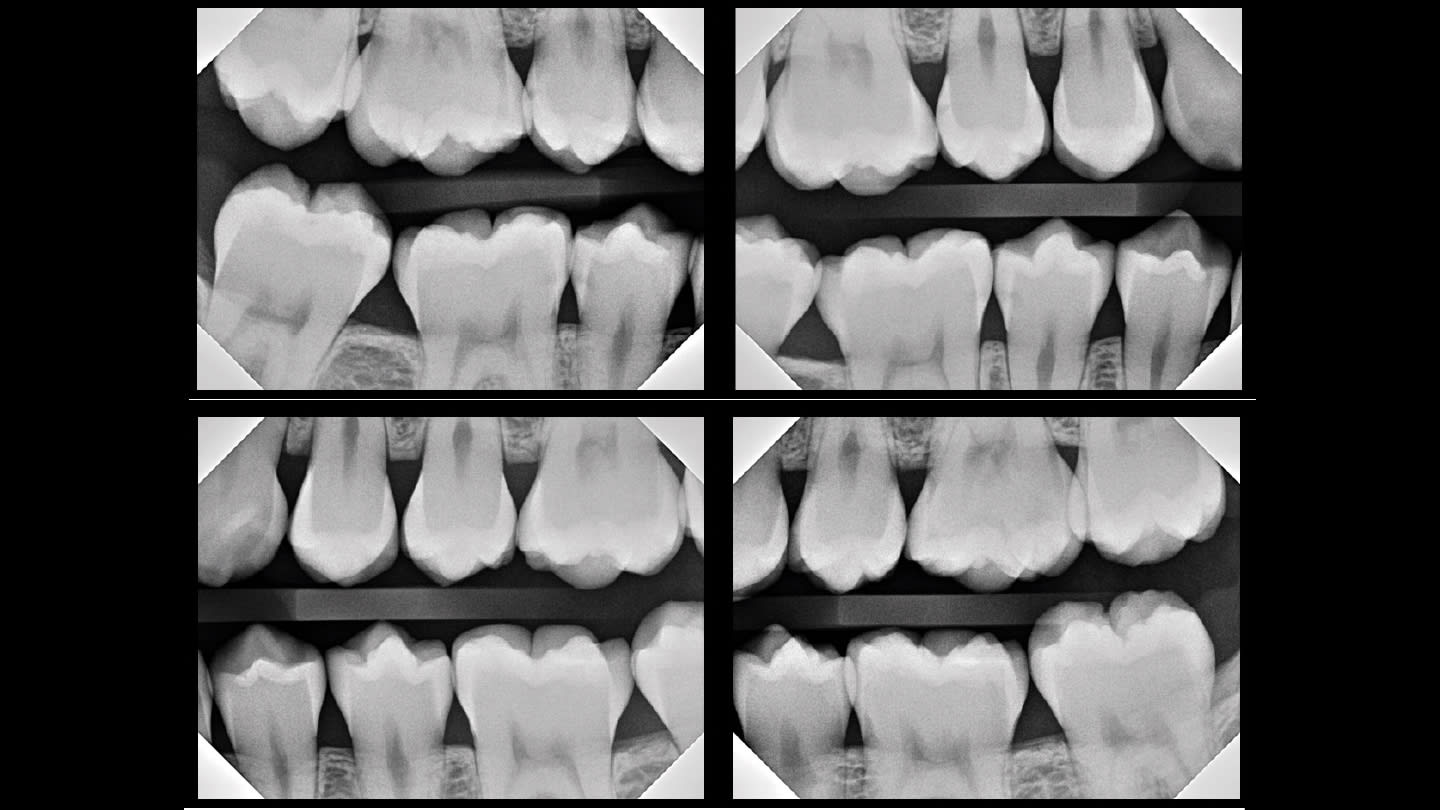

The way I was taught to treat class II lesions is antiquated, unpredictable, and barbaric. Take a look at the bitewings in Figure 1.

If you are anything like me, you would have recommended some watches, and some class II fillings. That’s what I did for over 20 years. And I now really regret it.

More than likely, the majority of you believe that #4, #29, #30 and #31 require some kind of intervention. At the very least, they shouldn’t be completely ignored. If you received your dental training similar to mine (I graduated from the University of Michigan in 2004), then it is within the realm of possibility that you would recommend quite a few MOs and DOs, maybe even an MOD for #30.